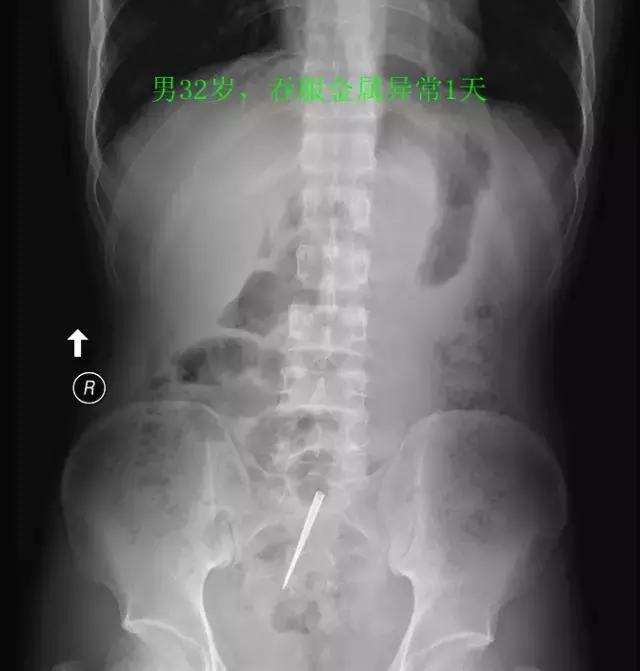

最后,是“看图识物”环节,请大家辨认下面三张图中的物体,欢迎在留言区发表你的看法哦。